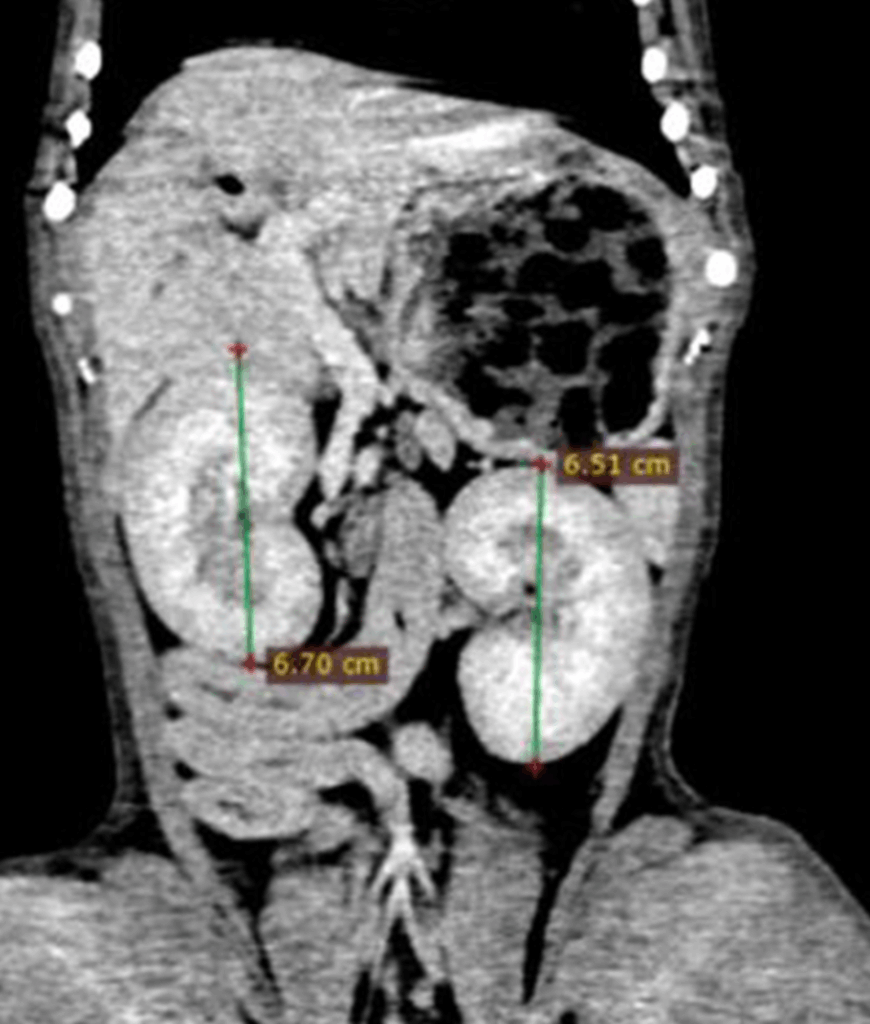

Uso de la portografía intraoperatoria en una anastomosis portosistémica intrahepática divisional izquierda

Paciente: Arnold, canino, macho, 8 meses, Bulldog Francés.

Signos de encefalopatía hepática. Retraso en crecimiento. Hematuria.